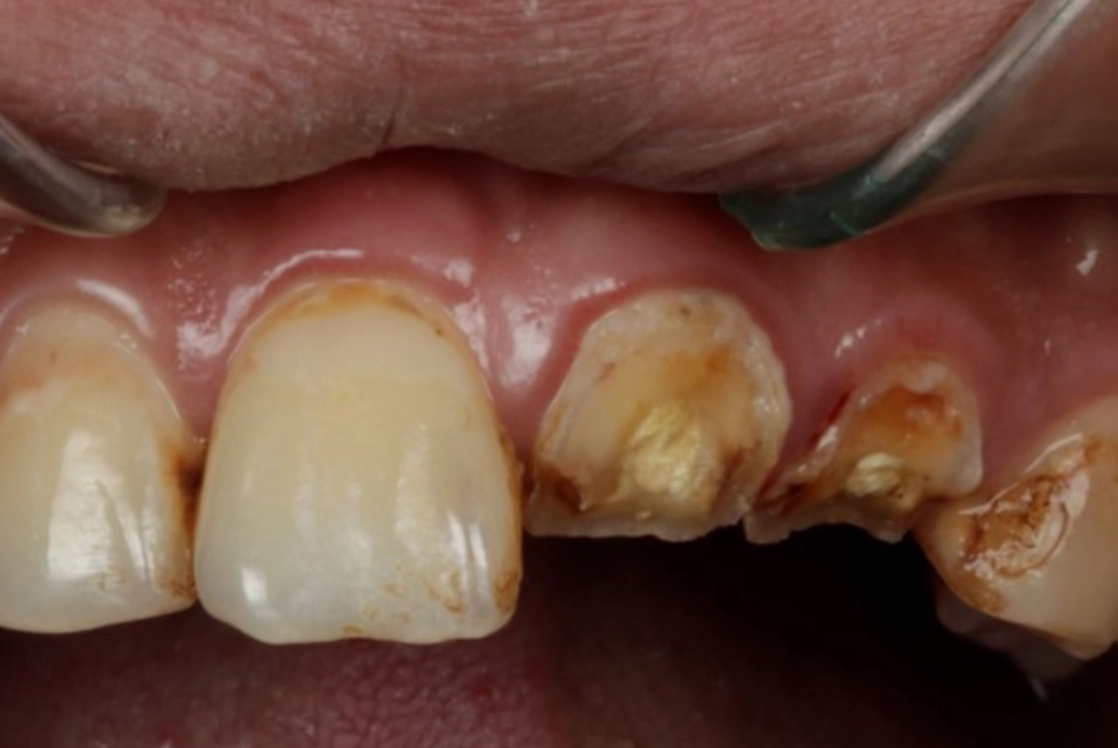

對,就是字面意思。排除生理原因永遠是第一步。夜間磨牙(學名:睡眠磨牙症)是導致牙齒斷裂的常見原因,而壓力正是磨牙的主要觸發因子之一。你可能完全沒意識到自己正在磨牙。

去看牙醫時,可以主動告知:「我最近夢到牙齒斷掉,有點擔心,可以請您幫我檢查是否有磨牙跡象或牙齒有隱裂嗎?」專業的牙醫能從琺瑯質磨損狀況判斷。如果真有磨牙問題,一副量身訂製的夜間牙套,既能保護你的牙齒,也從物理上中斷了「壓力→磨牙→夢到牙壞→更焦慮」的惡性循環。這是一個非常實際的自我照顧行動。